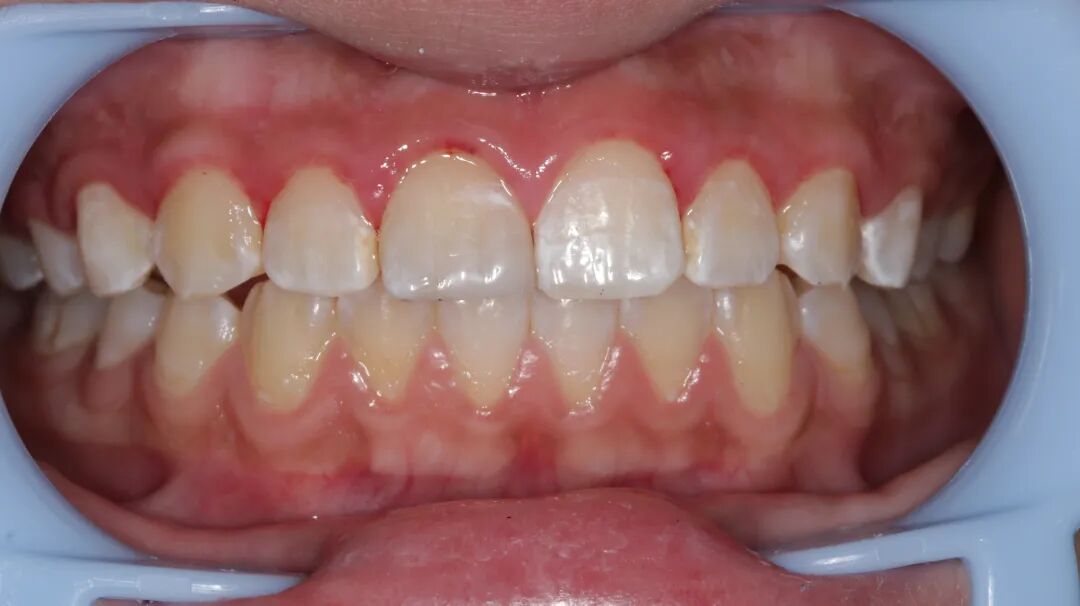

牙医-胡晨【实操病例】

上颌中切牙瓷贴面美学修复

性别:女     年龄21岁

主诉:前牙氟斑牙影响美观

现病史:病人因从小有高氟地区生活史,导致全口氟斑牙,现因前牙区氟斑牙呈黄褐色影响美观,要求处理

既往史:既往体健,否认疾病史及药物过敏史

检查:牙龈无红肿,口内卫生良好

治疗方案:铸瓷贴面美学修复